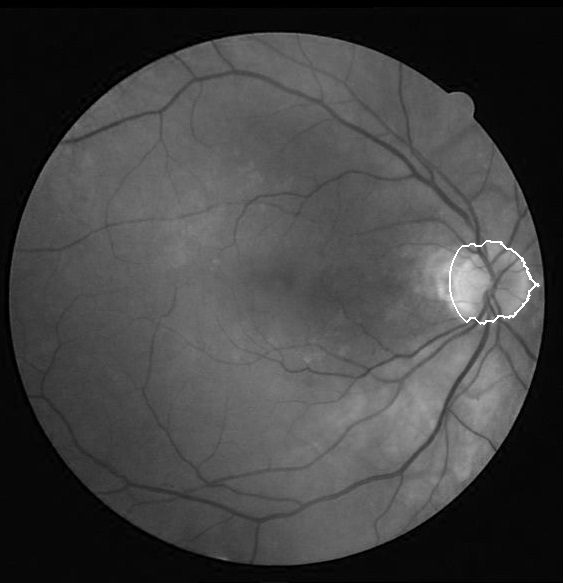

We applied our algorithm on 40 images of DRIVE dataset111http://www.isi.uu.nl/Research/Databases/DRIVE/and 50 images of Khatam database222Images of this database are gathered by Khatam-Al-Anbia eye hospital, Mashhad, Iran. In both datasets the optic disk boundary is hand labeled by an ophthalmologist as ground truth. Fig. 3 and Fig. 4 show our results on the DRIVE and Khatam databases respectively. The results show that our algorithm is robust to changing illumination and also to abnormal retinal images. The result on the second image of Khatam dataset (Fig. 3) shows that our algorithm can distinguish between parapapillary atrophy boundary and optic disk boundary.

In the first step, we need to define a window with the center of the optic disk. To accomplish this task, the center of the obtained region from the optic disk localization step is modified. The obtained region from the optic disk localization step is located at the temporal part of the optic disk. The reason is that this part is brighter than the other parts of the optic disk (superior, inferior and nasal parts. Fig 2), so the center of this area can approximate the center of optic disk height. But, this point can be the center of optic disk width if only the brightest part of the temporal side is close to the optic disk vessels. Therefore, by the information obtained from the vessel segmentation step, we adjust this point so that it gets close to the vessel. This point is used as the first estimation of optic disk center.

There are some characteristics which can be used to extract the optic disk. Sometimes, the optic disk area is brighter than its surrounding and it can be seen as a disk and in other images it appears as a hollow ring. Moreover, the optic disk part located on the temporal side is often more visible and brighter than the nasal part.